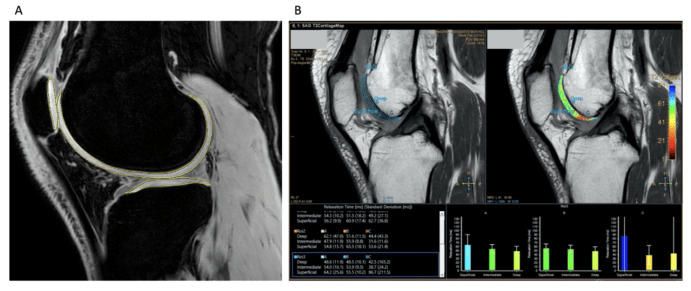

圖2:定量圖像MRI分析

• MAG200隊(duì)列報(bào)告的反應(yīng)者比例高于安慰劑組,并且疼痛癥狀有臨床和統(tǒng)計(jì)學(xué)顯著改善,所有KOOS分量表均有臨床相關(guān)改善。(圖2)

• MAG200顯示出優(yōu)于安慰劑的可重復(fù)治療效果,這對(duì)于10×106劑量組的疼痛具有臨床相關(guān)性,對(duì)于20×106和100×106劑量組的功能具有臨床相關(guān)性。

• 在MAG200 10、20和100 × 106劑量組中,觀察到疾病改善趨勢(shì),膝關(guān)節(jié)軟骨總體積有所改善,而安慰劑組中骨關(guān)節(jié)炎有輕微改善。